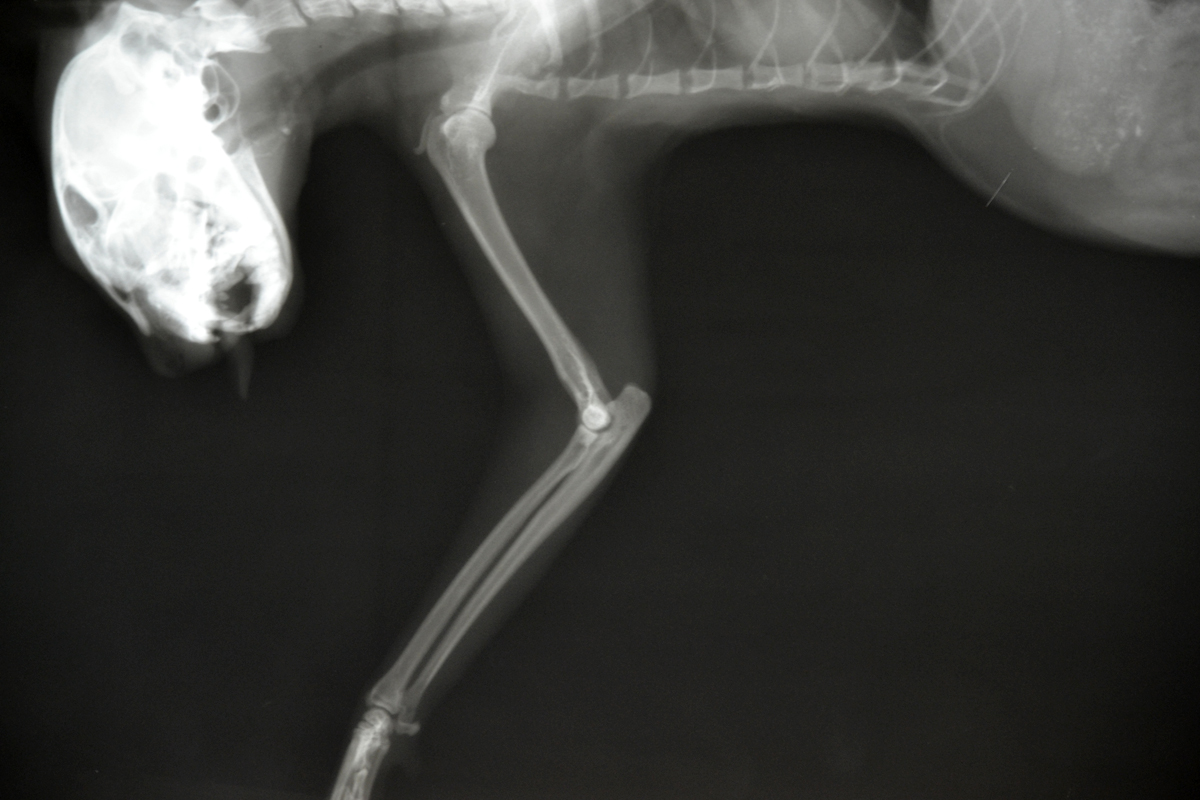

Рентгеновские снимки перелома лапы у кота: диагностика и лечение